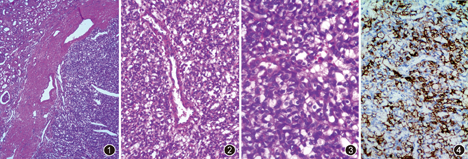

病理检查:大体观察:左侧肾脏切除标本,大小13.0 cm×7.0 cm×5.0 cm,肾上极距被膜0.8 cm切面见一大小2.5 cm×2.0 cm×2.0 cm的灰黄肿物,质地较软,与周围组织境界清楚,无包膜。镜下观察:低倍境下肿瘤境界相对清楚,由厚的纤维性假包膜包绕,瘤细胞弥漫分布,被薄壁血管分割(图1);瘤细胞围绕树枝状、血管外皮细胞瘤样大血管呈放射状生长(图2);部分区域间质水肿、透明样变或硬化,细胞丰富区和稀少区交替,水肿或硬化区域瘤细胞散在,但网状血管丰富;瘤细胞圆形、卵圆形或多角形,胞质嗜酸或部分胞质内含有脂质空泡(图3)。免疫组织化学检测:波形蛋白、PAX–8、S–100蛋白、α–抑制素(图4)及神经元特异性烯醇化酶(NSE)均弥漫阳性,上皮细胞膜抗原(EMA)和CD10局灶阳性,CD34血管阳性,其余广谱细胞角蛋白(CKpan)、平滑肌肌动蛋白(SMA)、HMB–45、突触素、嗜铬粒素A、WT–1及Calretinin均阴性,Ki–67阳性指数1%。

病理诊断:散发性血管母细胞瘤。